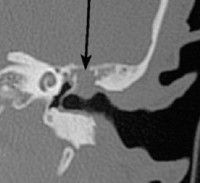

К диагностике холестеатомы уха могут привлекаться не только отоларингологи, но также неврологи и нейрохирурги. Зачастую признаки холестеатомы уха можно обнаружить при рентгенографии черепа. На рентгенограммах в проекции по Майеру, Шюллеру или Стенверсу холестеатома определяется как имеющая среднюю плотность однородная тень, которая находится в круглой патологической полости с гладкими и четко визуализирующимися краями. Более точную визуальную картину образования получают при проведении КТ и МСКТ черепа.